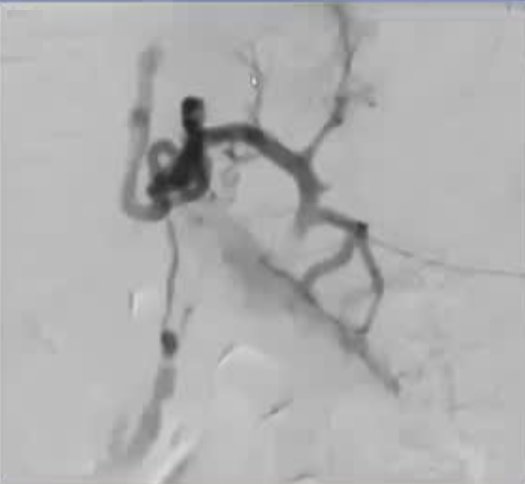

急性门静脉血栓(续) 对于那些成功实施经颈静脉经肝到达门静脉内急性血栓内,并进行了溶栓和抗凝治疗的患者,是否应该进行经颈静脉肝内门体分流术(TIPS)呢(放支架)? 这一问题存在争议。 。一个过于激进的TIPS手术,导致门静脉分支没有血流,从而发展成肝硬化 妥协的操作是设置一个“小TIPS”,即放置一个直径较细(直径5毫米左右)的TIPS裸支架,溶栓导管经支架通过,进行抗凝和溶栓治疗后,同时保留 TJ 对 SMV/PV 的访问权限,以防再次发生血栓情况。 一例术后急性门静脉血栓病例,最终影像显示门静脉根部血流情况良好,这还不够理想,担心会再次发生血栓,且门静脉压(PSG)超过 12 毫米汞柱,因此增加了经导管动脉溶栓术(TIPS)的治疗方案。

急性病例,已有肠道缺血的迹象,经皮穿刺入路,尿激酶溶栓(t-PA),血流不畅,转为经颈静脉肝内门体分流术(TIPS),抗凝治疗